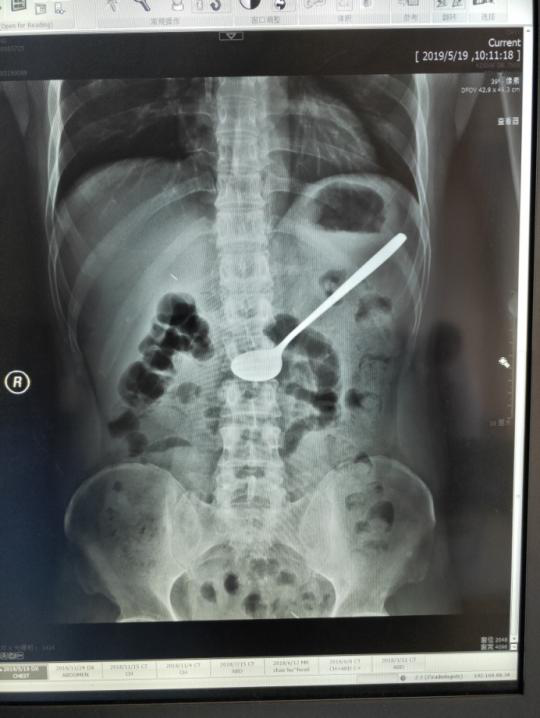

安徽商报:难以置信!胃镜下取出20cm长铁勺

519上午,安医大附属巢湖医院消化内科主任(兼内镜中心主任)李仁君在胃镜室成功为一名患者进行了高难度的胃镜下取异物术,取出了患者吞下的20cm的铁勺。

5月19日上午,像往常一样,消化内科主任李仁君在诊室忙碌的接诊。11时,诊室进来一位面容十分痛苦,捂着肚子满头大汗的患者,通过问诊,患者在5月18日下午误吞了一个长约20cm的铁质汤勺,曾求治过数家医院,均表示无法取出,并建议到上级医院进行外科手术治疗。于是,患者来到安医大附属巢湖医院胃肠外科就诊,经过X线检查未见消化道穿孔,见异物仍滞留于胃腔,考虑患者基础有尿毒症病史,如果进行胃部手术的话,对于患者来说术后创伤大,恢复期长,并发症多,并不是最佳治疗手段。遂请消化内科会诊评估能否内镜下处理。患者经过一天的转诊,已经身心疲惫,此时腹痛难忍。

李仁君主任接诊后,考虑患者吞服的为一个长约20cm的金属汤勺,表面光滑,无明显受力点,且重量大,普通的异物钳及网篮均无法有效取出。同时,患者又有尿毒症病史,长期进行着透析治疗,疾病决定了患者消化道管壁脆弱,操作不慎容易导致消化道粘膜损伤,严重者可以导致穿孔,尤其在通过贲门、食管中段及入口三处狭窄部时候更应注意。经过充分的综合考虑,与家属沟通征求同意后,李主任果断决定尝试通过内镜取出异物。

李仁君经过积极准备,选择圈套器这一少用的工具,并且将术中的配合注意事项告知配合助手柯晓琴护士。操作中,他发现患者胃腔内还有少许未消化的食物,汤勺部分淹没在食物腔内,便使用圈套器缓慢伸入,然后张开,从勺处缓慢向勺柄移动,利用胃镜前端的长透明帽将汤勺与消化道管腔成水平方向。在通过贲门及食管入口时候利用胃镜的左右方向键尽量减少食管损伤。经过20分钟左右时间,终于成功取出了这个大家伙。时间虽短,但整个操作过程必须加倍小心仔细,轻柔操作,否则会对患者造成二次伤害。